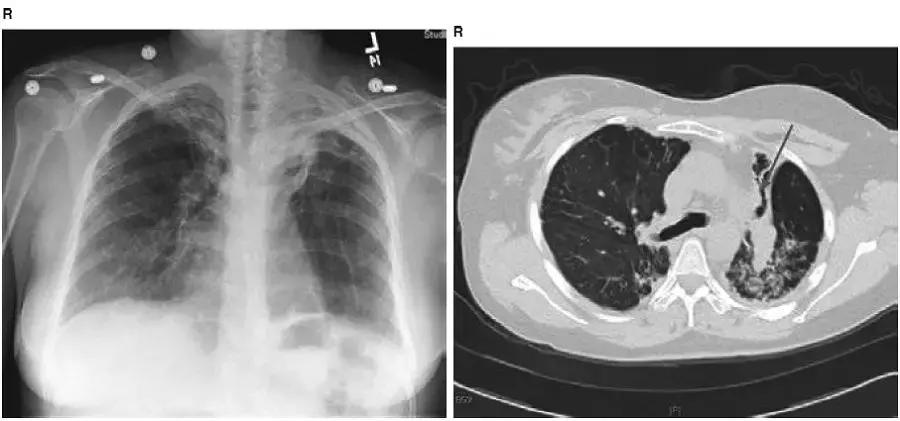

图4-7 胸片显示右肺上叶肺不张(黄箭头)。右侧膈肌抬高和纵隔向右移位使肺容积减少。胸片清楚显示气管内导管(红箭头)和中心静脉导管(黑箭头)

图4-8 胸片显示右肺上叶病变:右侧膈肌、水平裂抬高(黄箭头)和气管右侧移位(蓝箭头)导致肺容积缩小